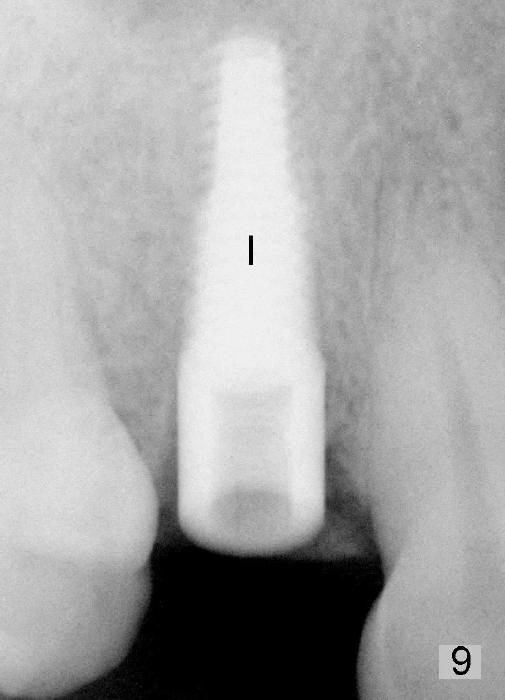

The patient returns 6 months postop for impression of a permanent restoration. The gingiva with knife-edged papillae adapts to the provisional (Fig.7). The gingiva looks healthy when the provisional is removed (Fig.8). The buccal bone resorption seems to be minimal, as compared to Fig.1,2. There is no bone loss between immediately postop (Fig.9 I; implant), 4.5 months postop (Fig.10 A: abutment), 4 and 7 months post cementation (Fig.11,12 C: crown). Soft and hard tissue morphology remains normal 7 months post cementation (Fig.13). No bone loss is observed 15 months post cementation (Fig.14). The papillae (Fig.15) and bone (Fig.16,17) remain stable 29 months post cementation.